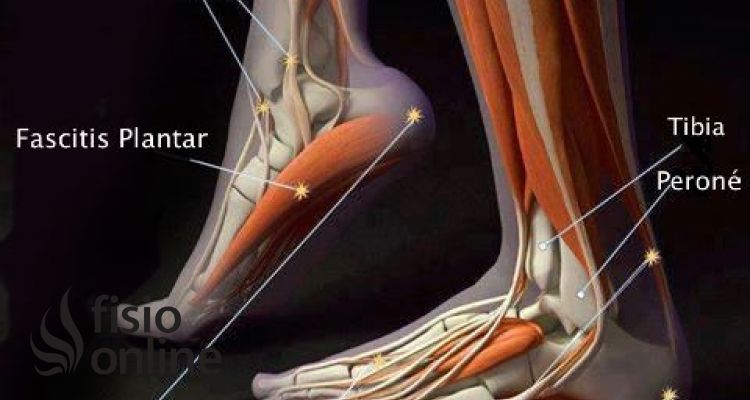

Las infografías, tienen como objetivo llamar la atención sobre aspectos importantes, que pensamos son necesarios tener en cuenta como interesado o como paciente, mediante esta forma gráfica y visual pretendemos lanzar mensajes clave para hacerte recapacitar y poner en cuestión diferentes aspectos, tanto sobre patologías y/o lesiones, como sobre otros temas relacionados con la salud, como por ejemplo, la alimentación, el ejercicio físico o la salud mental.

En nuestras infografias encontrarás consejos para cuidarte, información sobre causas, consecuencias y tratamiento de lesiones, herramientas que puedes utilizar si sufres una lesión o patología, y nuestra opinión sobre diferentes temas relacionados con la salud. Consideramos que lo importante es, que se despierte en ti la curiosidad por tu salud y que empieces a cuidarte.